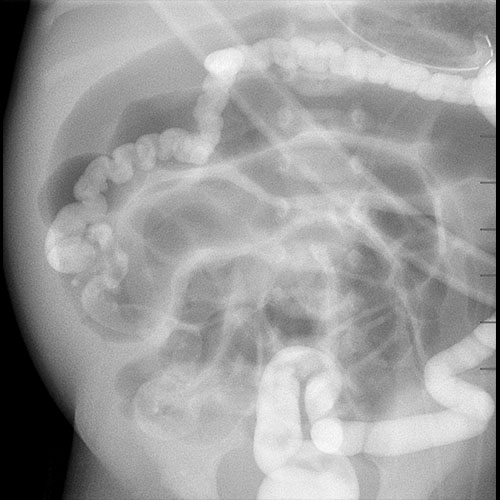

KUB/Supine Abdomen.

Scout Image of the abdomen

There is dilatation with gas or fluid of multiple or diffuse loops of bowel.

​Both the small and large bowel are filled with air and/or fluid and may or may not be distended.

There are centralized loops of small bowel with distention of the abdomen and pelvis.